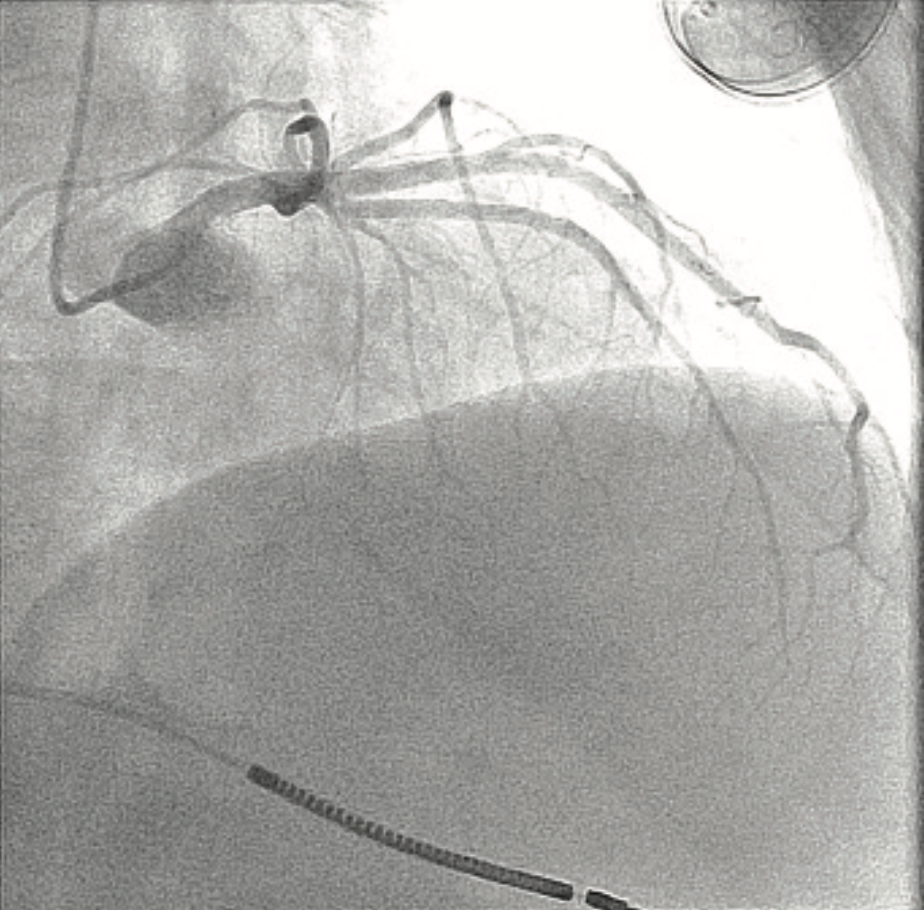

For mitral valve procedures, we use the ACIST to determine the mitral annular plane. It definitely requires high-flow injections, because there is a lot of volume going through the mitral valve. You also have to switch from doing a left atrial angiogram, which requires maybe 10 ccs of contrast, to doing a left ventriculogram, which requires maybe 10-20 ccs of contrast. The ACIST permits us to move between those injections quickly. If you are trying to characterize the left or right atrium in a transseptal procedure, it can easily be done with the ACIST. Another advantage of the ACIST is that because it offers higher and more consistent flow than with a hand injection, I can keep my small catheter in place and still get an optimal result. We also use the ACIST for left atrial appendage closures (Image 1). Using pre-procedural CT scans, the Philips system allows you to overlay your CT images onto the fluoroscopic image. Using an ACIST contrast injection hooked up to the Philips system, you can also do a rotational angiogram to generate a 3D image. We have also used the ACIST for pulmonary angiograms (Images 2-3) and pulmonary stenting. The images show a case of a patient who presented with acute chest pain. We were able to image his coronaries and when these proved to be normal, we performed a pulmonary angiogram in the same setting. For pulmonary valve stenting, you definitely need a contrast injection in the right ventricular outflow tract to make sure you have the necessary size and space. If you do a coarct stent as well, you want a high-flow injection to characterize the anatomy. I was involved in stem cell studies a few years ago, and in determining the sites for injection, we would perform a left ventriculogram to characterize where we want to inject cells, and quickly move to a coronary injection to guide our injections, without having to change the system between angiograms.

This is a 79-year-old woman with emphysema, arthritis, and severe aortic stenosis, and she needed a TAVR. There were several issues with her TAVR: one was that her coronary heights were low. If you put a TAVR valve in a patient with very low coronary heights, there is a chance that the native valve will get pushed up and occlude the coronary artery. We’ve had that happen once before, and the patient died from it, so it is a very serious complication. We did a novel procedure called the bioprosthetic aortic scallop intentional laceration to prevent iatrogenic coronary artery obstruction (BASILICA) procedure, where you slice the leaflet of the native aortic valve in half. Even though the leaflet gets pushed up, since it has been sliced in half, it won’t occlude the coronary artery. We first needed to look at her coronary arteries and the cusps using 3-6 cc coronary injections, and then we performed the BASILICA procedure. The patient also had an anomalous takeoff of her carotid arteries. We wanted to use a carotid embolic protection device, but because she had such an anomalous takeoff, it had to be placed in a very unique way. We did have a CT scan and had to correlate it with the patient so we would know exactly where to put the device. We needed to take an arch angiogram, which is a higher power contrast injection, 10 for 15 ccs or 10 for 20 ccs. The TAVR procedure was done as usual, using the 10 cc contrast injection I described earlier, to measure the annulus planes and look at implant depth. Then we looked at the coronary arteries, because it turned out that the patient needed a stent in her coronary artery. At the end of the case, we wanted to make sure that our closure of the large-bore access sheath was sufficient, so we flipped down to the leg and took a picture there using digital subtraction angiography and a 2 cc injection. I’ll share a second case that also demonstrates the versatility of the ACIST (Images 2-6). This was a patient with acute shortness of breath and chest pain, and there was a question of whether he was having a pulmonary embolus or a heart attack. The electrocardiogram was unclear. We took him back to the lab and were able to do a pulmonary angiogram, then visualize the coronaries, all on one setting. We also did an iliac angiogram, because we used that access in order to give him a support device. This case required pulmonary (Images 2-3), coronary (Images 4-5), and iliac angiograms (Image 6), all done with use of the ACIST CVi system.